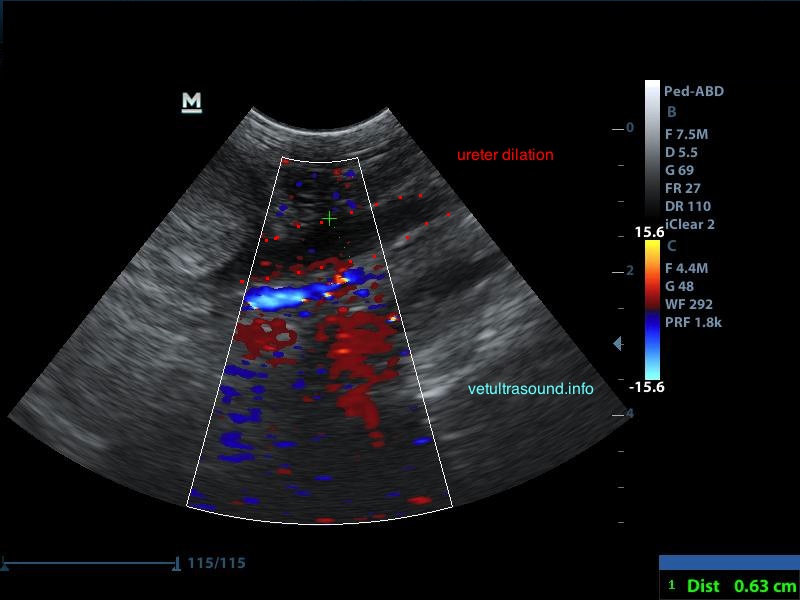

Ευρήματα: Στον υπέρηχο κοιλίας βρέθηκε επώδυνη διόγκωση και των δύο νεφρών με πάχυνση της φλοιώδους ουσίας, η οποία παρουσίαζε έντονη ανομοιογένεια. Οι νεφρικές πύελοι ήταν ήπια διατεταμένοι και στο εσωτερικό τους παρατηρήθηκε αφθονία ιζήματος. Οι ουρητήρες, οι οποίοι ήταν επίσης διατεταμένοι, απεικονίζονταν μέχρι την είσοδό τους στην ουροδόχο κύστη. Αφθονία ιζήματος βρέθηκε στην ουροδόχο κύστη. Η εικόνα αυτή είναι συμβατή με διάμεση νεφρίτιδα και στην συγκεκριμένη περίπτωση με πυοκοκκιωματώδη φλεγμονή των νεφρών, συνεκτιμώντας τα εργαστηριακά ευρήματα, τον έντονο πόνο και τη διάταση των ουρητήρων. Το resistive index ( δείκτης αγγειακής αντίστασης) βρέθηκε αυξημένο (0.77) σε μεσολόβιο αρτηρίδιο του νεφρού. Φυσιολογικά θα έπρεπε να είναι (0.6±0.06). Αυτό δείχνει πως το οίδημα του νεφρικού παρεγχύματος εξαιτίας φλεγμονής ή οποιαδήποτε άλλης διήθησης, νεοπλασματικής ή μη, πιέζει τα αγγεία και αυξάνει την αντίσταση του αίματος προς το νεφρό. Ένα επιπλέον διαγνωστικό βήμα για την διερεύνηση της αιτίας, για την αποτελεσματικότερη θεραπεία και την εγκυρότερη πρόγνωση, είναι η λήψη κυτταρολογικού υλικού από το νεφρικό παρέγχυμα και ούρου από τη νεφρική πύελο για καλλιέργεια, στα οποία ο ιδιοκτήτης δεν θέλησε να προχωρήσει.